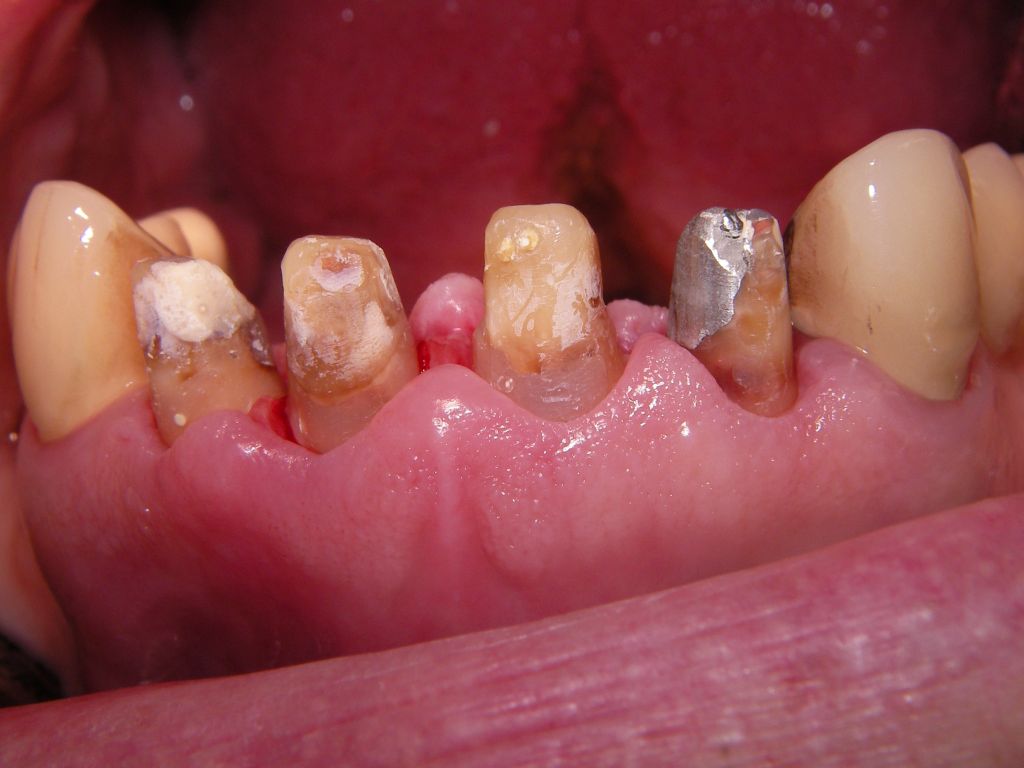

Allerdings kann man diesen Metallrand auch sehr schmal gestalten, wie das folgende Beispiel zeigt. Wegen der starken Zerstörungen mußte der Kronenrand tief unter das Zahnfleisch gelegt werden. Das ist einerseits ungünstig, weil es Zahnfleischentzündungen fördern kann (die hier aber nicht zu sehen sind), andererseits günstig, weil nicht zu befürchten ist, daß das Zahnfleisch so weit zurückgehen wird, daß man den Kronenrand sehen wird.

Oft ist nach vielen Jahren aber gar nicht die Krone das Problem, sondern die dunkle Zahnwurzel, die vom Zahnfleisch entblößt wird. Wie man unten sieht, sind insbesondere wurzelbehandelte Zähne sehr dunkel. Hier hilft dann doch nur wieder, mit dem Kronenrand tief unter das Zahnfleisch zu gehen, um die dunkle Wurzel abzudecken.

Weil auch die anderen Schneidezahnkronen (12-22) durch Randreparaturen und den schlechten Randschluß erneuerungsbedürftig aussahen, wurden 4 Einzelkronen geplant. Vorher hieß es aber noch, die schlechte Wurzelfüllung im Zahn 12 (Röntgenbild links) besser zu machen. Hierfür wurden am 17.2.06 die alten Kronen 11 und 12 entfernt. Rechts das Bild nach Entfernung von alten Füllungen und Karies.

Links das Kontrollfoto nach der Sitzung am 17.2.06. Damit war die Vorbehandlung in diesem Fall abgeschlossen. Am 28.2.06 erfolgte die endgültige Präparation (das "Beschleifen") aller 4 Zähne. Links das Modell, auf dem die Kronen gefertigt worden waren. Rechts kurz vorm Zementieren der Kronen am 13.3.06. Aus der Längendifferenz der Zähne rechts und links kann man darauf schließen, daß die Präparation tief unter dem Zahnfleisch erfolgen mußte.